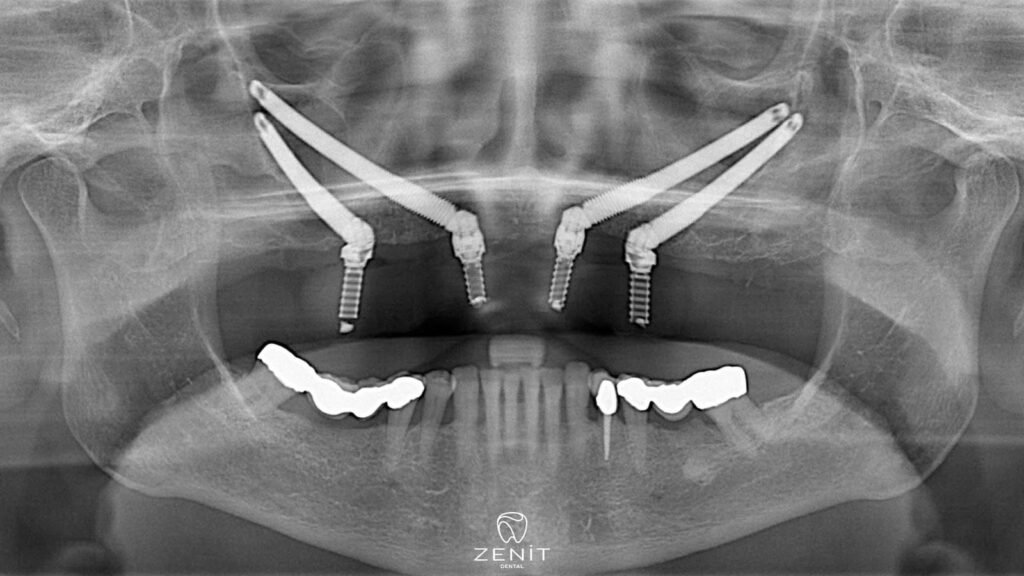

Zigoma implantları, çene kemiği yetersiz olan hastalar için mükemmel bir alternatif sunar ve yüz bölgesinde devrim niteliğinde bir tedavi sağlar. Bu özel implantlar, geleneksel implantlardan farklı olarak üst çene kemiği yerine elmacık (zigoma) kemiğine yerleştirilir. Elmacık kemiği, çene kemiğine göre daha yoğun ve güçlü bir yapıya sahip olduğundan, zigoma implantlar bu bölgeye güvenle yerleştirilebilir. Zigoma implantları sayesinde, ileri derecede kemik kaybı yaşayan hastalar bile, estetik ve fonksiyonel olarak tatmin edici sonuçlara ulaşabilirler.

Elmacık kemiğine yerleştirilen zigoma implantlar, diğer dental implantlardan farklı olarak, çene kemiğine değil, yüzün orta kısmında bulunan ve oldukça sağlam bir yapıya sahip olan zigomatik kemik denilen bölgeye yerleştirilir. Zigomatik kemik, diğer kemiklerden daha yoğun bir yapıya sahiptir ve genellikle kemik kaybı yaşanmaz. Bu özelliği sayesinde, zigoma implantları çene kemiği yetersizliği olan hastalara güvenli ve etkili bir çözüm sunar.

- İmplant Yerleştirme: Zigoma implantlar, üst çene kemiği yerine elmacık kemiğine yerleştirilir. Cerrah, implantları yerleştirirken yüksek hassasiyetle çalışır, çünkü zigomatik bölgeye ulaşmak ve implantları doğru pozisyonda yerleştirmek oldukça dikkat gerektirir.